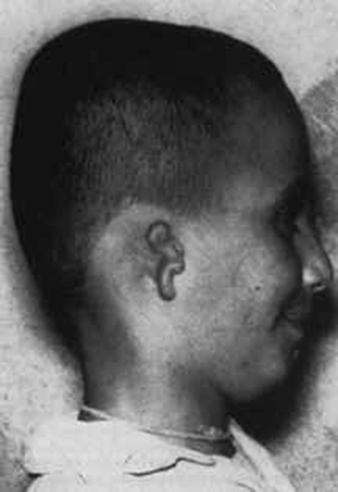

图八显示了一个土耳其男孩的头部右侧有一个缩小变形的耳朵(单侧小耳)。头部右侧还欠发育(半边脸小)。他说他记得一个男人的生平,那个男人被用霰弹枪近距离射击。他被送到医院并在6天后因为穿透右侧颅骨的射击造成的脑部受伤去世(我得到了这个案例的医院记录)。

图八,一位土耳其男孩严重变形的耳朵(小耳)。他说他记得一个男人的生平,那个男人被近距离发射的霰弹击伤右侧头部而死亡。(图片来源:childpastlives)